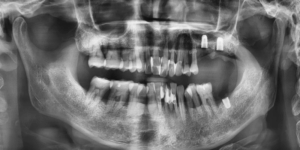

이후 환자분은 6년 동안 매우 성실하게

치주치료와 유지관리를 이어가셨고

그 결과 대부분의 치아에서 치조골 재생이

관찰될 만큼 건강한 상태로 회복되었습니다.

전악발치가 필요하다는 절망적 상황에서

꾸준한 치료를 통해 본인의 자연치아를

대부분 유지할 수 있었다는 점은

환자분에게 큰 만족감을 주었습니다.